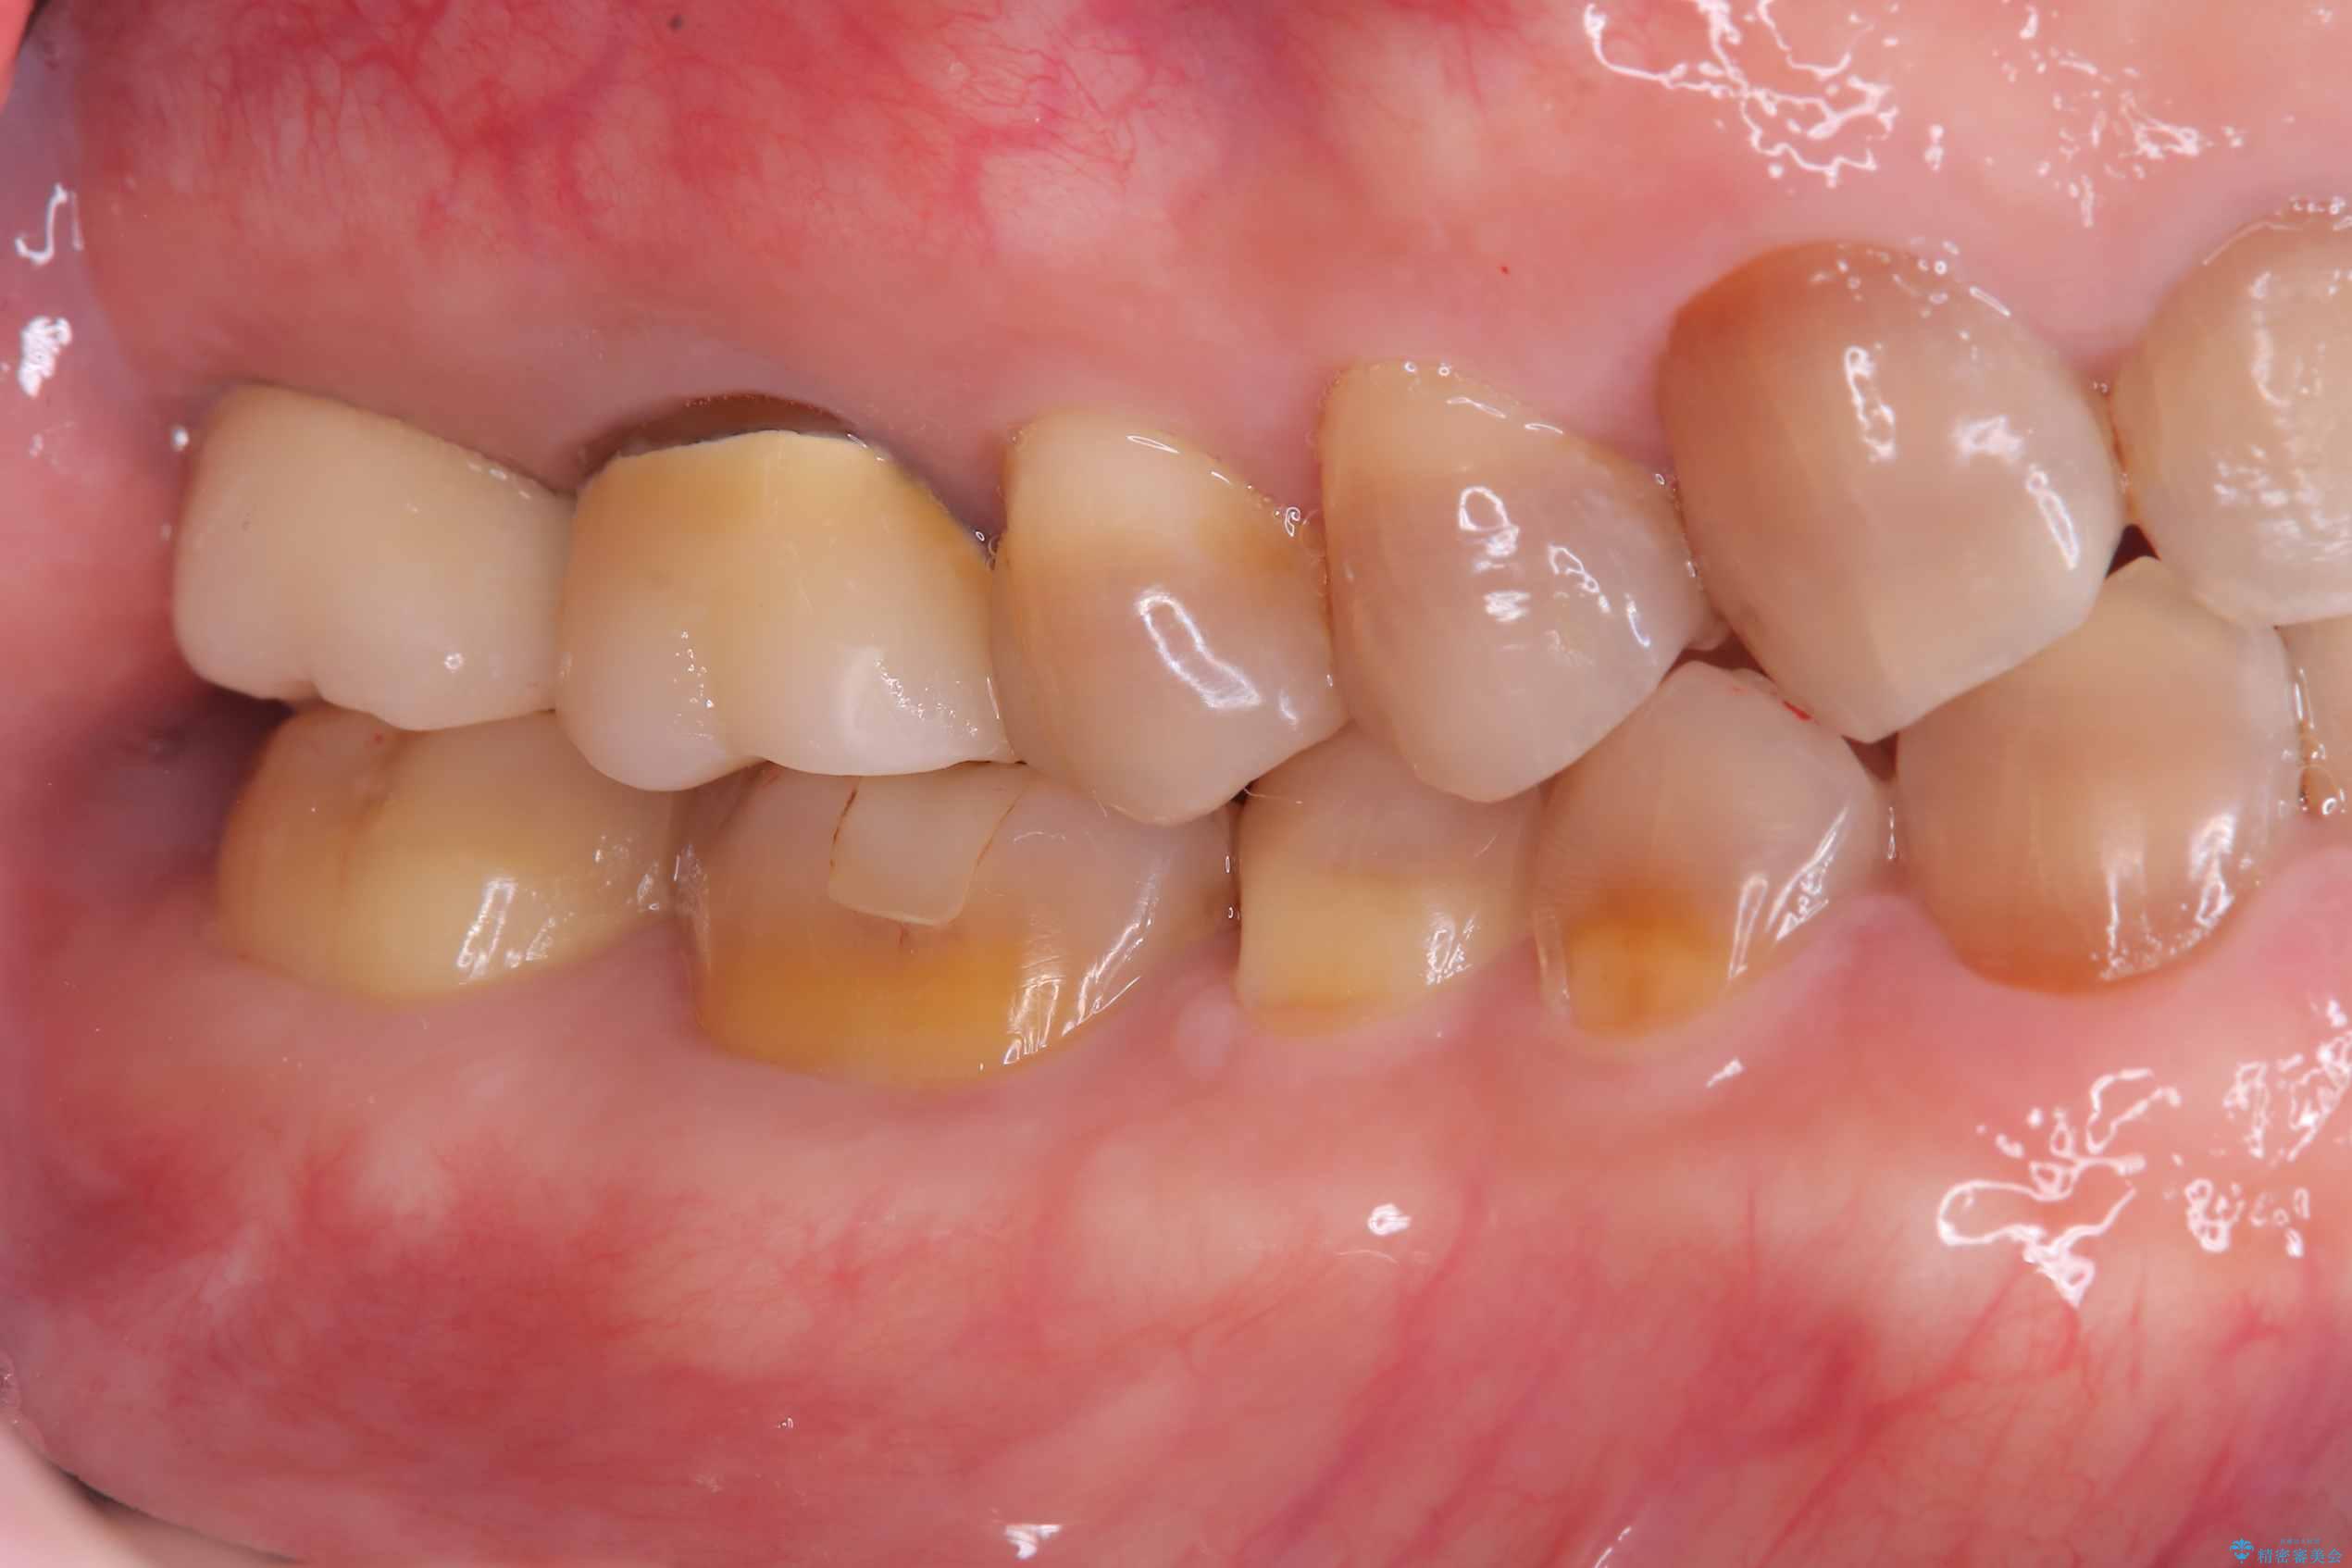

- 治療計画

- 右上7番に瘻孔を認め、根管治療を実施しましたが、瘻孔が再発し治癒が得られなかったため、抜歯のうえインプラントによる補綴治療を行いました。

抜歯と歯根嚢胞の除去を行った後、インプラントで治療しました。治療後は「自分の歯のように咬める」と大変ご満足いただけました。